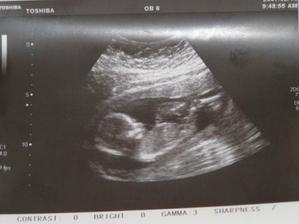

SRPŇÁTKA 2007 - fotky UTZ

album věnované mimískům, které se narodí v srpnu 2007 a jejich maminkám ze "Společného termínu SRPEN"